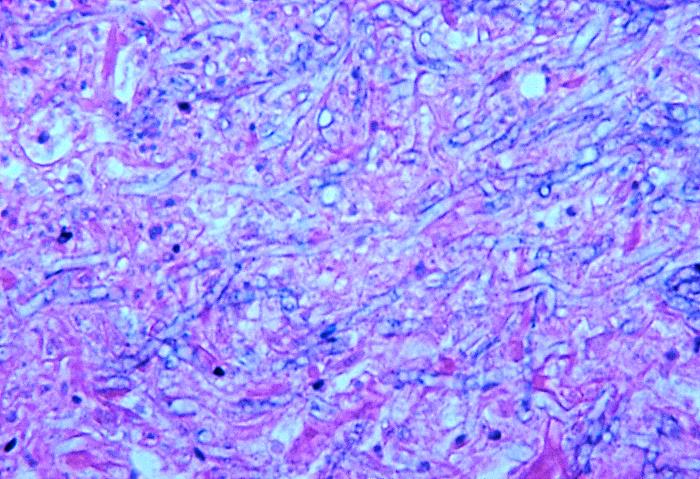

其次,觀察菌絲結構是診斷肺曲菌病的關鍵。曲霉菌的菌絲在顯微鏡下呈現為分隔狀,且分生孢子頭具有典型的特征。通過觀察頂囊上的小梗層數、小梗分布范圍、殼細胞有無結合以及分生孢子的特征,可以對肺曲霉菌的種類進行鑒定。這些特征對于區(qū)分曲霉菌與其他真菌種類至關重要。

此外,在肺曲菌病的病理切片中,還可以觀察到與菌絲侵入血管腔相關的壞死灶和出血灶。當曲霉菌感染涉及大動脈時,可能會出現楔形梗塞。這些梗塞可能進一步導致進行性空洞的形成,進而可能發(fā)展為真菌球。這些病理變化是肺曲菌病在顯微鏡下的典型表現。